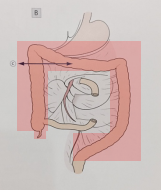

经过3周的肠外营养支持治疗,患者生命体征平稳,复查血指标恢复至大致正常范围内,我科为其进行了腹腔镜下全结肠切除、回肠储袋肛门吻合(ileal pouch-anal anastomosis-IPAA)、近端回肠造口手术。

手术切除的范围     末端回肠折叠制作储袋、进行肛管储袋吻合